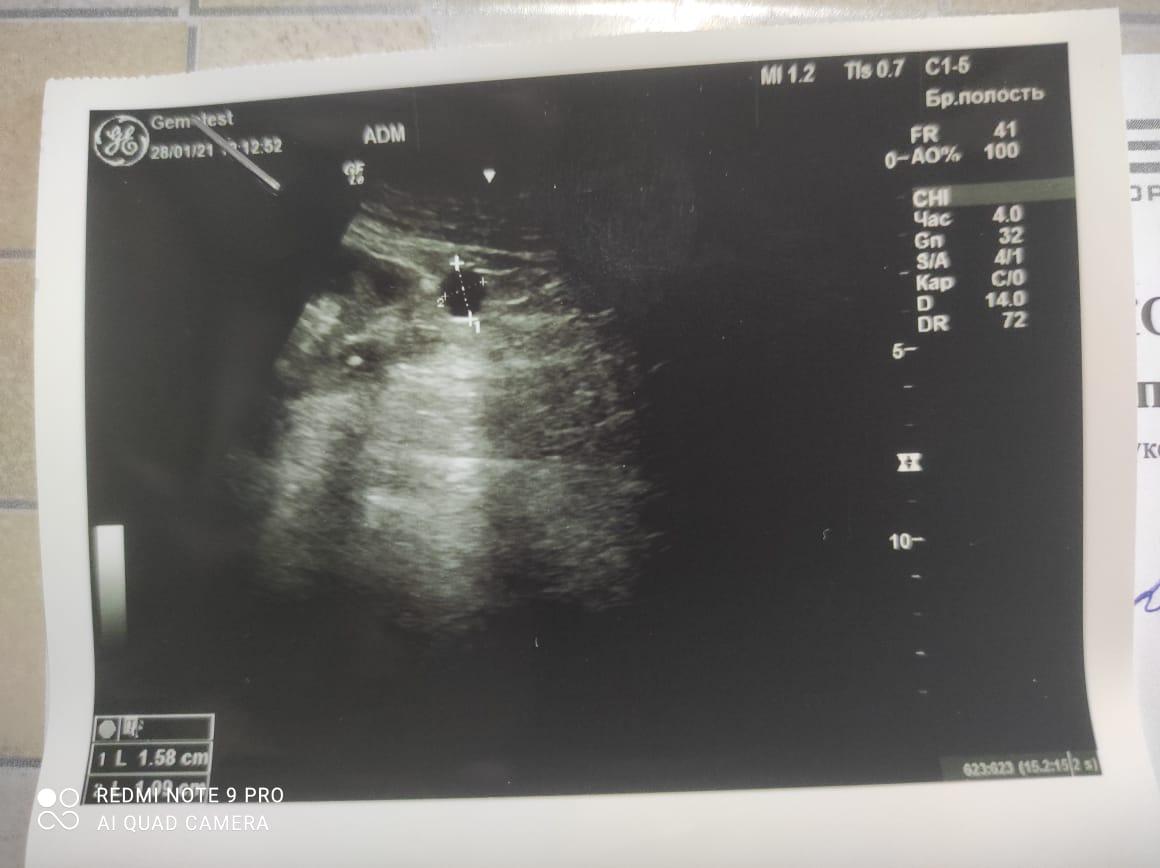

Здравствуйте! При наличии коралловидного камня правой почки(заключение УЗИ), можно предположить причиной боли нарушение уродинамики верхних мочевых путей), что, однако, не подтверждается результатами УЗИ почек( ЧЛС не расширена). Другая, наиболее вероятная возможная причина "боли в боку" - может быть патология опорнодвигательного аппарата. Необходимо проконсультироваться с неврологом и урологом очно, и согласовать возможность применения противовоспалительных, обезболивающих и спазмолитических препаратов - как первый шаг. В дальнейшем необходимо планировать возможное дальнейшее обследование и лечение. Удачи!